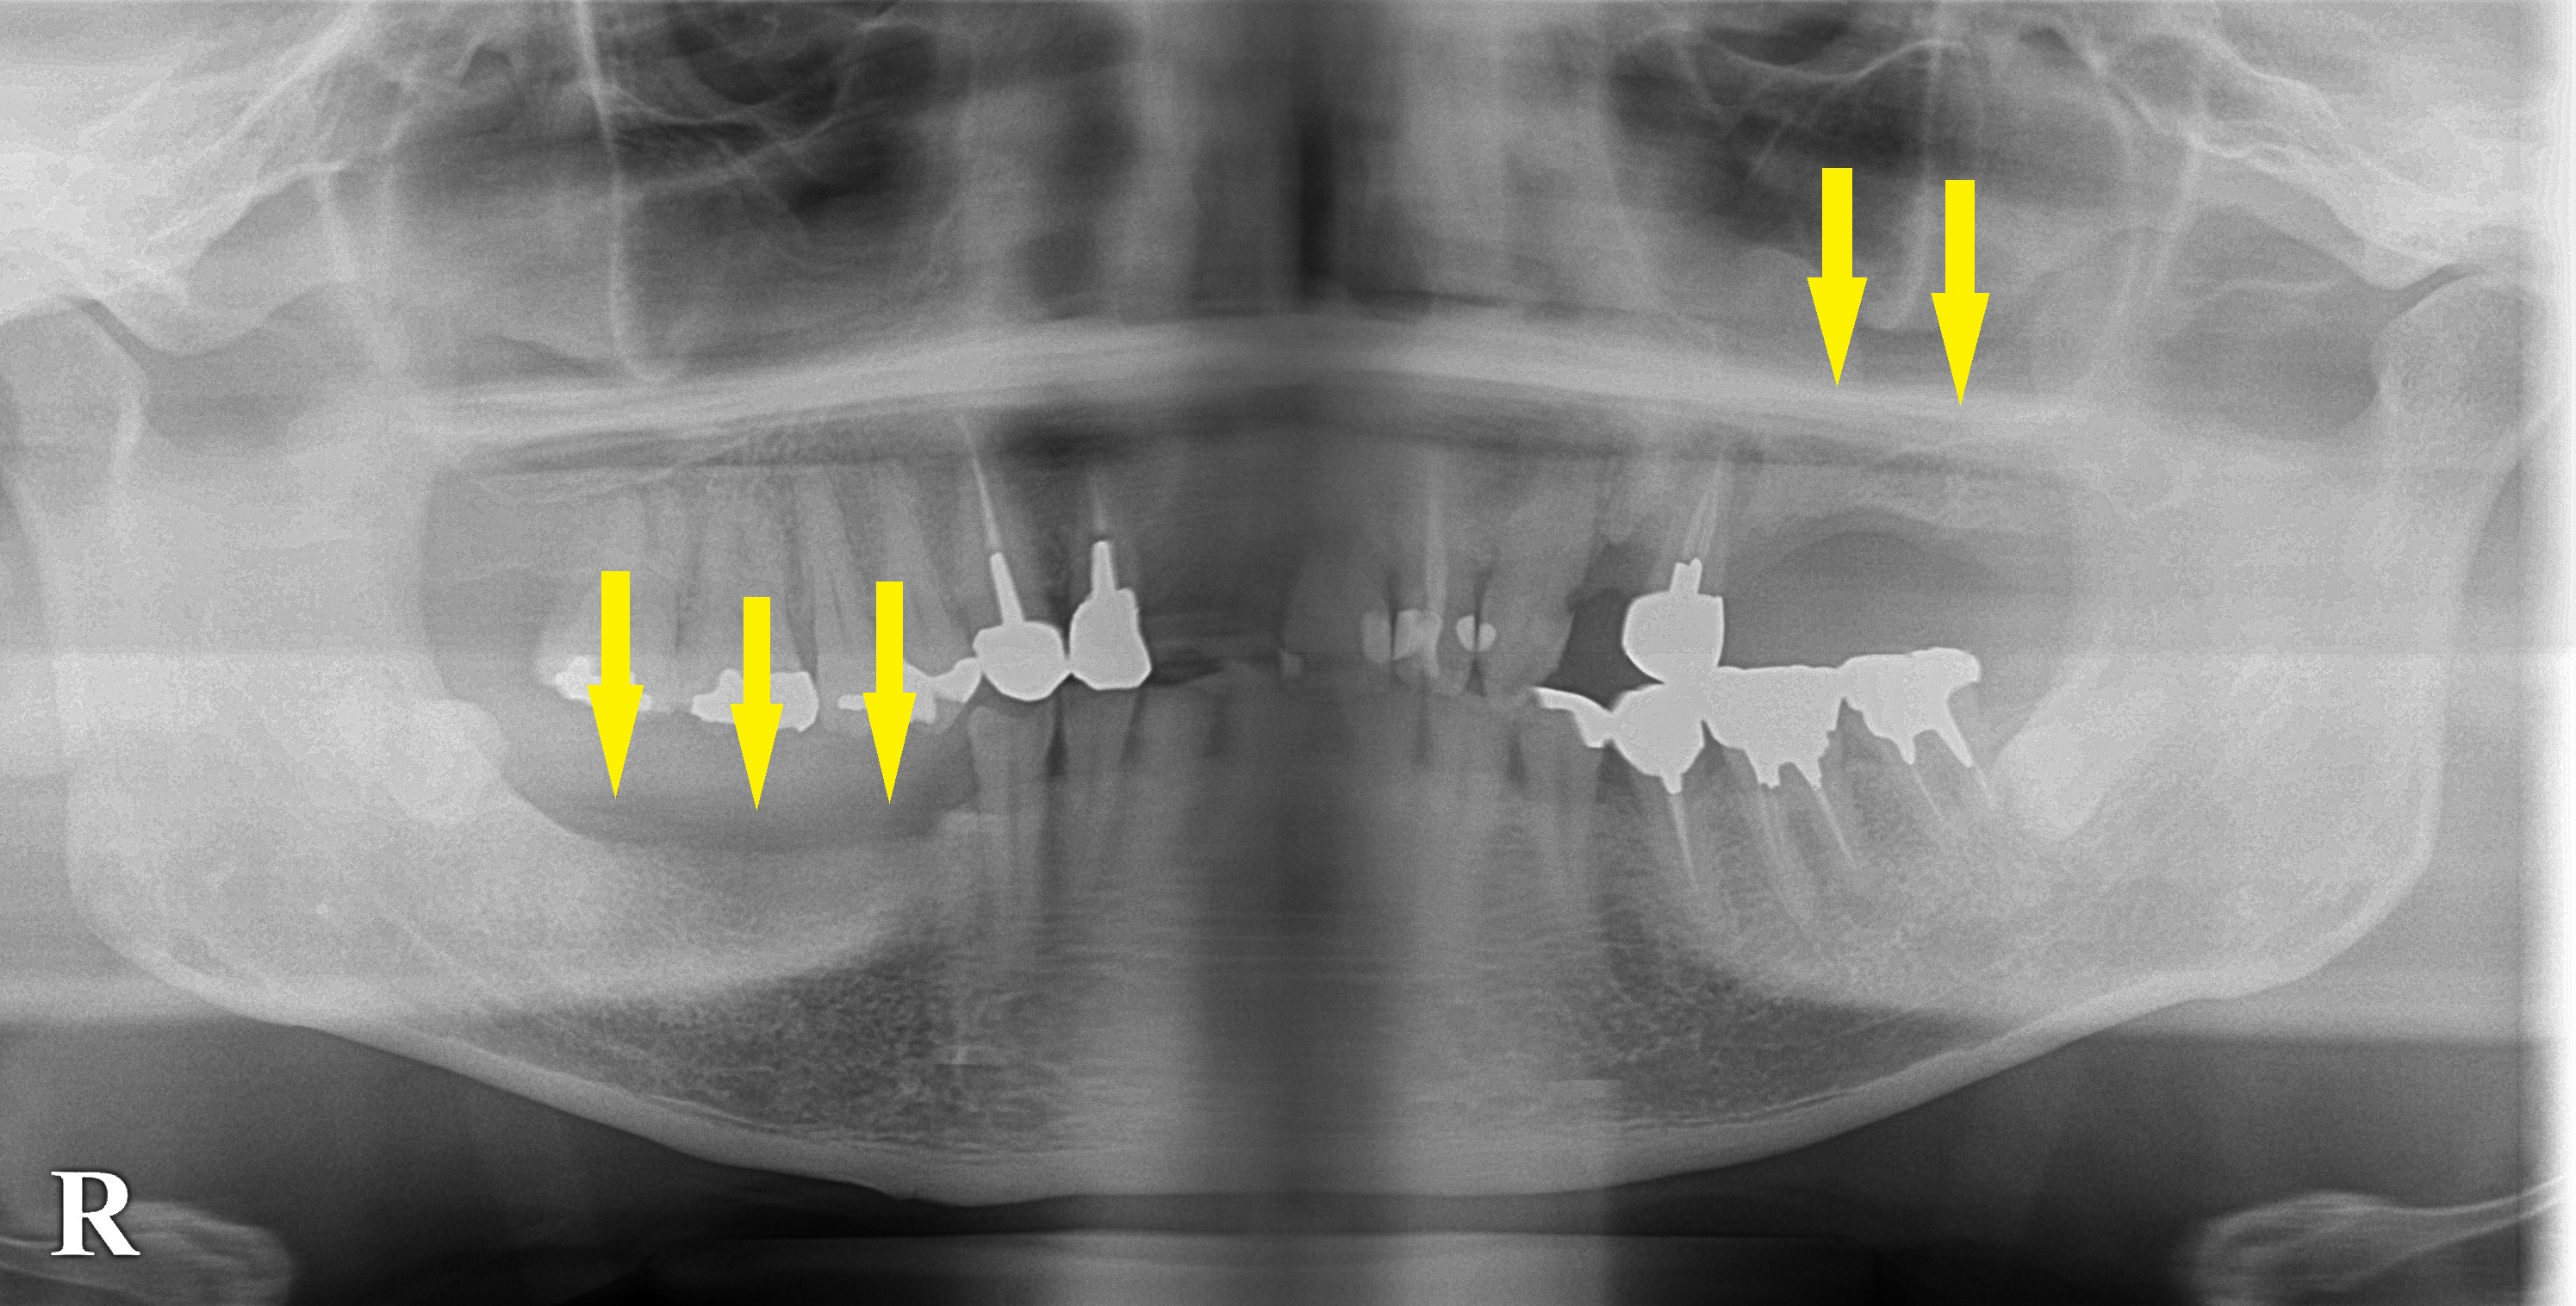

左上顎と右下顎の臼歯がなくて、義歯を装着されていたそうですが、具合が悪くインプラント治療を希望されて来院されました。

右下顎は骨量に問題はありませんが、左上顎は骨がやや薄くなんらかの骨造成が必要と思われました。

まずは臼歯で咬めるところを作るために、本日、右下顎に3本のインプラント埋入術を行いました。

左上顎は、骨造成を行ってのインプラント治療予定です。

CT画像|インプラント治療で選ばれる名古屋の歯科医院